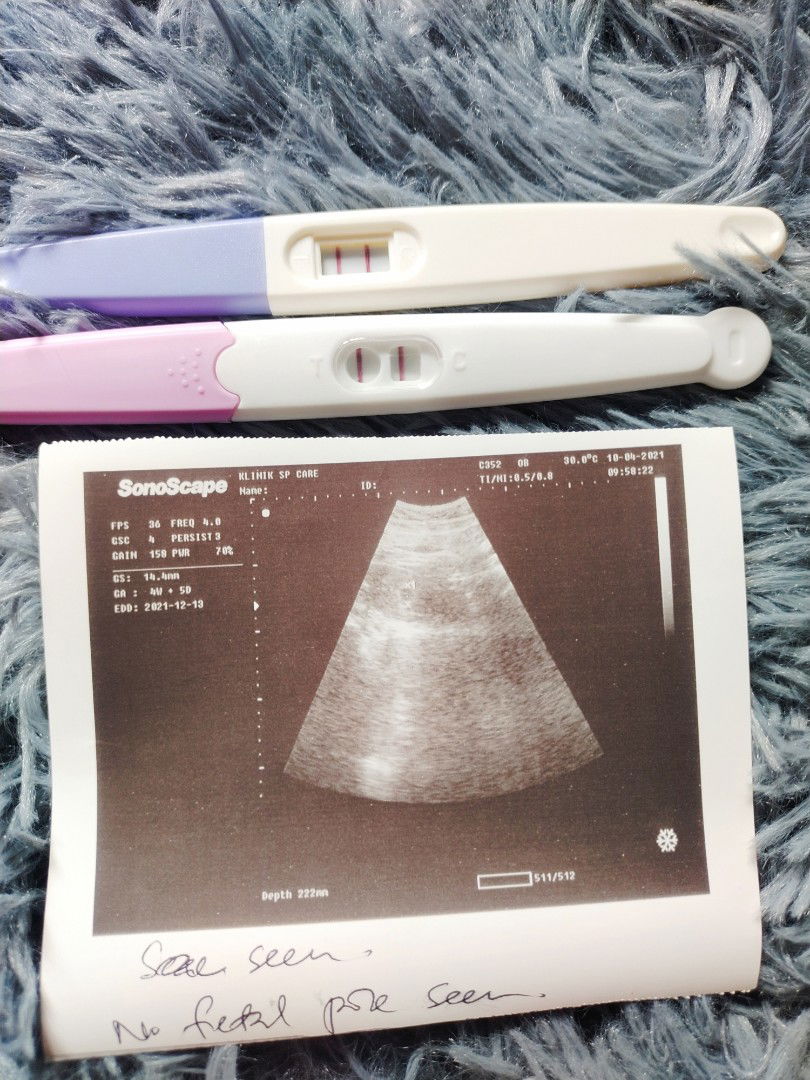

Perlu Minum Susu Usia Kandung 4minggu ?

Hi , Boleh Saya Tanye ? Kalau Kandung Baru 4minggu , Perlu ke Saya Minum Susu ? Boleh Bantu Saya Cara Pjagaan Baru 4minggu Nie ..